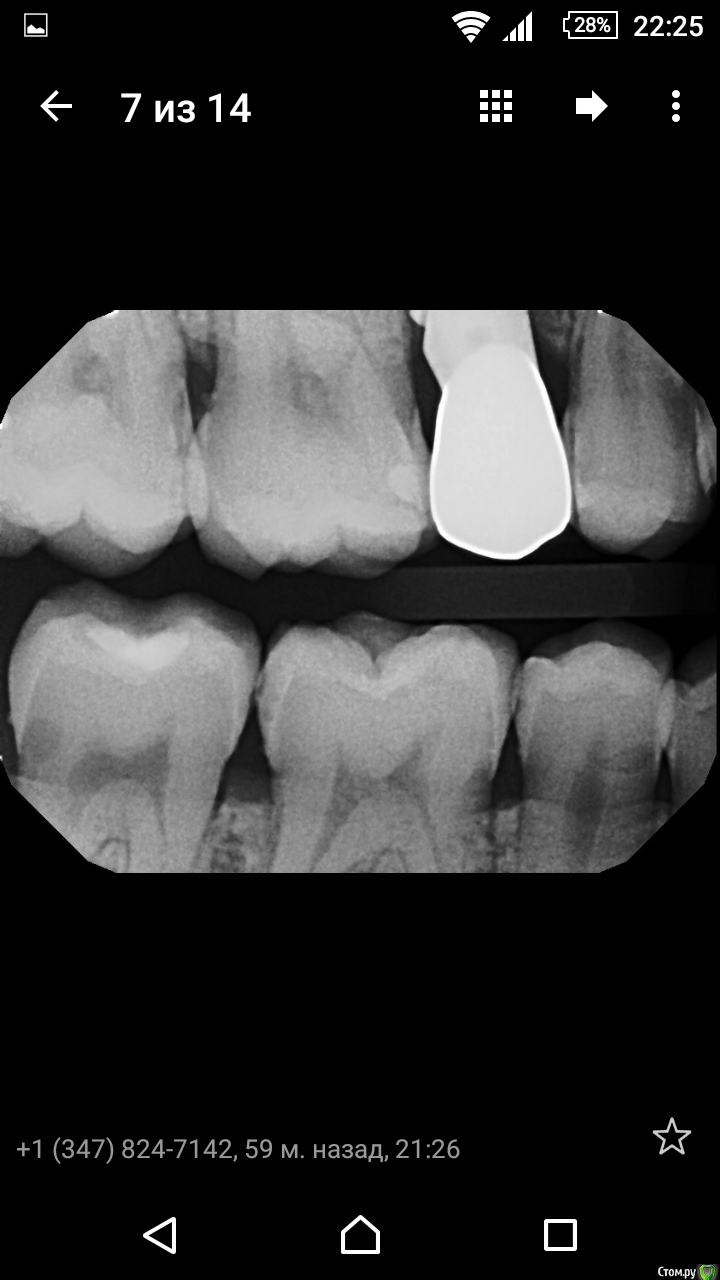

Карен Аванесов Опубликовано 19 февраля, 2016 Поделиться Опубликовано 19 февраля, 2016 (изменено) Вообще такие темы гадалки, без продолжения бесят. Вызывайте свою подруги и запиливайте подозреваемые зубы (на некоторых, нижних что то есть), для удовлетворения любопытства. Ну или американец таки сорвет фишку. Вот тут есть кариес (точнее уже нет), жалобы были. Изменено 19 февраля, 2016 пользователем Карен Аванесов Ссылка на комментарий

Shaid Опубликовано 24 февраля, 2016 Поделиться Опубликовано 24 февраля, 2016 Карен, на втором фото у Вас дистальная матрица так и осталась стоять или потом подправили? Я имею ввиду прилегание. Ссылка на комментарий

Карен Аванесов Опубликовано 24 февраля, 2016 Поделиться Опубликовано 24 февраля, 2016 Это без оптики делал и фото как альтернатива, увеличил снимок увидел где не так и додавил. Ссылка на комментарий

Shaid Опубликовано 24 февраля, 2016 Поделиться Опубликовано 24 февраля, 2016 додавил. фумкой? Ссылка на комментарий

Карен Аванесов Опубликовано 24 февраля, 2016 Поделиться Опубликовано 24 февраля, 2016 сначала уз по краю потом клин Ссылка на комментарий